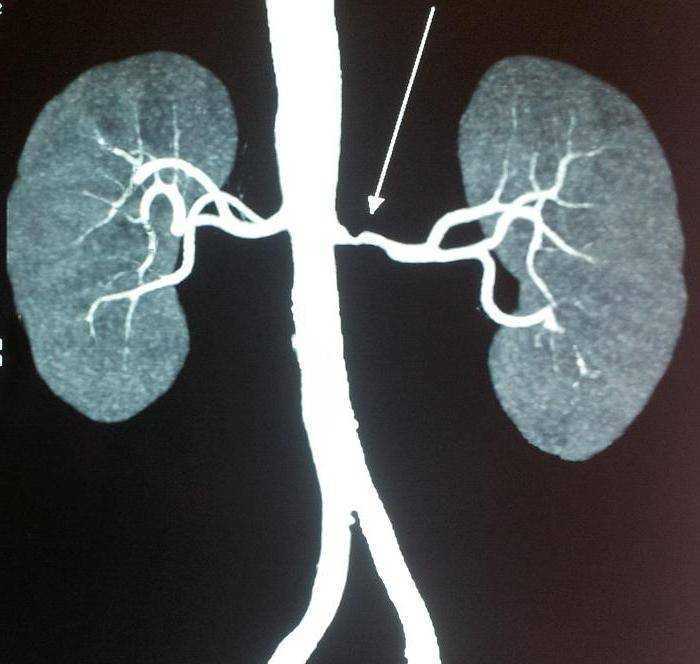

ЦДК сосудов почек: что это и как проводится